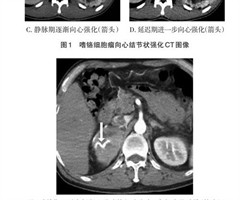

嗜铬细胞瘤及副神经节瘤不同生化表型的CT征象对比研究

【摘要】目的:分析生化阴性嗜铬细胞瘤及副神经节瘤(pheochromocytomas and paragangliomas,PPGLs)的电子计算机断层扫描(computed tomography,CT)征象是否有别于生化阳性PPGLs,同...